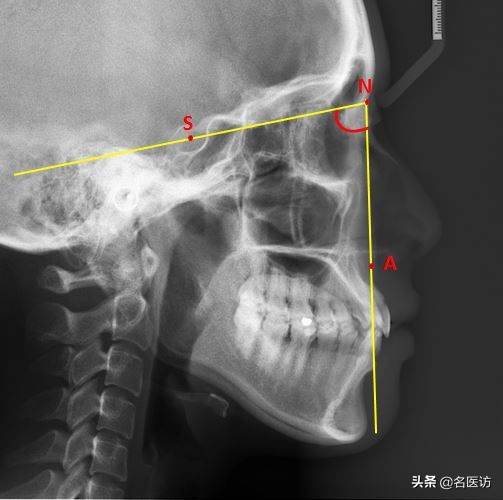

2、评估下颌位置:SNB角

B:下牙槽座点,下牙槽和颏部接触的最凹点

当该角过大时下颌相对前颅底的位置前突;反之呈颌后缩。